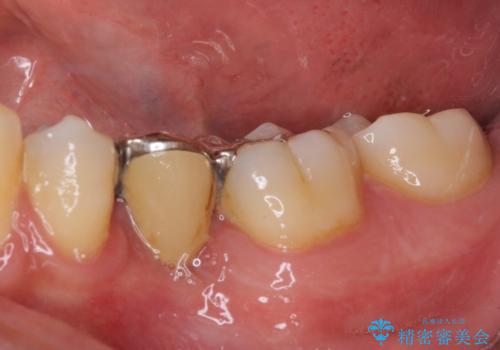

- 奥歯の銀歯が頻繁に外れるとのことで来院された患者様です。

欠損部分をインレーによるブリッジで治療してありましたが、外れやすく虫歯リスクが高いため、オールセラミックブリッジにて補綴することとしました。